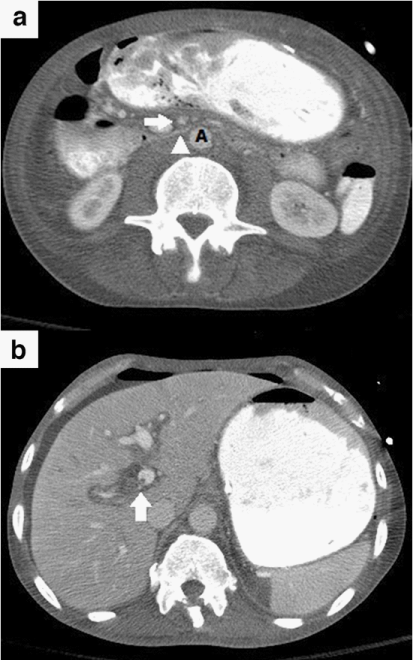

A 62 year-old African American man presented with periumbilical abdominal pain, nausea and bilious, non-bloody vomiting for two days. One month prior to presentation he was evaluated for a four-month history of watery, non-mucoid diarrhea with associated 15 lb unintentional weight loss. This workup included stool studies, colonoscopy, and CT of the abdomen, all of which were normal. His medical history was notable for uncontrolled diabetes mellitus type II, seizure disorder, and untreated hepatitis C. On examination he was a cachectic male with a calculated BMI of 14.8. He was hemodynamically stable and afebrile, with a diffusely tender abdomen and voluntary guarding. There were no stigmata of liver disease. Laboratory studies revealed a leukocytosis of 15.9; however an extensive infectious work-up including blood, urine and peritoneal cultures was negative. Liver function tests, amylase, lipase, and lactate levels were all normal. A CT of the abdomen revealed narrowing of the distance between the SMA and the aorta at the level of the 3rd portion of the duodenum (Figure 1a), with associated dilation of the stomach and proximal duodenum. These findings were consistent with SMA syndrome. Also seen were non-occlusive thrombi in the branches of the portal vein consistent with acute PVT (Figure 1b). Finally, mild compression of the distal superior mesenteric vein (SMV) was appreciated on CT. An abdominal ultrasound revealed a decreased SMA-aortic angle of 16-24 degrees (Figure 2a) and a distance between the two measuring 6mm (Figure 2b), thereby confirming the diagnosis of SMA syndrome.4 Esophagogastroduodenoscopy (EGD) was subsequently performed, revealing a dilated stomach with large amounts of gastric contents. A decompressive gastrostomy tube with a feeding jejunal extension was placed. The patient was managed medically with anticoagulation and empiric antibiotics and demonstrated clinical improvement. He was subsequently discharged to a nursing facility following a 2 week hospitalization; the gastrojejunostomy tube was kept in place on discharge. The patient returned to the hospital 2 months later with urosepsis further complicated by diabetic ketoacidosis and uncontrolled seizures. The patient ultimately expired from these comorbid illnesses before follow-up imaging could be obtained.

Figure 1 (a) Axial contrast CT image demonstrates narrowing of the distance between the superior mesenteric artery (arrow) and the aorta (A) at the level of the third portion of the duodenum (arrowhead). Also note the distention of the stomach and first and second portions of the duodenum proximal to the level of the crossing superior mesenteric artery.

(b) Axial Contrast CT image obtained during the portal venous phase demonstrates a non-occlusive thrombus within the right portal vein (arrow).